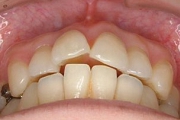

CASE4

前歯で物が噛み切れない。 顔が曲がって見える。

右のアゴが たまに痛い。

(19歳/女性)↓

||||||||

概要・担当医コメント:

開咬/下顎の左右的偏位/顎関節症/非抜歯

動的治療期間28ヶ月(28回)/費用概算:65万円

顎関節症の改善を主目的として治療を開始しました.歯科矯正用アンカースクリューを使用することにより,上下とも非抜歯で治療出来ました.大臼歯の上下的位置を調整することで,顎関節に負担のかかり過ぎない噛み合わせにしました.